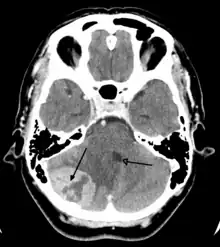

Imaging

Medical imaging plays a central role in the diagnosis of brain tumors. Early imaging methods – invasive and sometimes dangerous – such as pneumoencephalography and cerebral angiography have been replaced by non-invasive, high-resolution techniques, especially magnetic resonance imaging (MRI) and computed tomography (CT) scans.[42] MRI with contrast enhancement is the preferred imaging test in the diagnosis of brain tumors.[24][43] Glioblastomas usually enhance with contrast on T1 MRI weighted MRI imaging, and on T2 with FLAIR imaging showing hyperintense cerebral edema.[24] Low grade gliomas are usually hypointense on T1 MRI, and hyperintense with T2 with FLAIR MRI. Meningiomas are usually homogenously enhanced with dural thickening on MRI.[24]

Computed Tomography (CT) Scan – uses x-rays to take pictures from different angles and computer processing to combine the pictures into a 3D image. A CT scan usually serves as an alternative to MRI in cases where the patient cannot have an MRI due to claustrophobia or pacemaker. Compared to MRI, a CT scan shows a more detailed image of the bone structures near the tumor and can be used to measure the tumor's size.[51] Like an MRI, a contrast dye may also be injected into the veins or ingested by mouth before a CT scan to better outline any tumors that may be present. CT scans use contrast materials that are iodine-based and barium sulfate compounds. The downside of using CT scans as opposed to MRI is that some brain tumors do not show up well on CT scans because some intra-axial masses are faint and resemble normal brain tissue. In some scenarios, brain tumors in CT scans may be mistaken for infarction, infection, and demyelination. To suspect that an intra-axial mass is a brain tumor instead of other possibilities, there must be unexplained calcifications in the brain, preservation of the cortex, and disproportionate mass effect.[52]